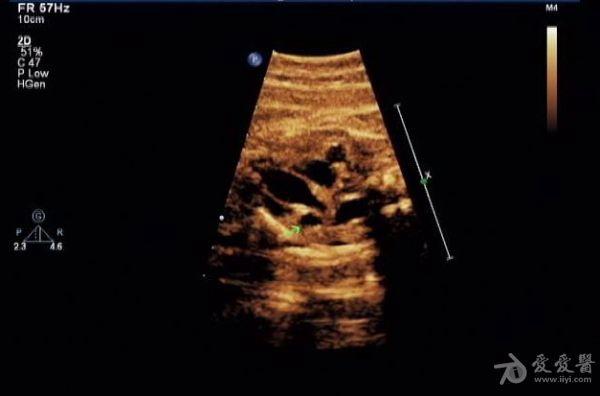

胎儿永存上腔静脉

冠状静脉窦增宽约

0.8 cm

,心底部三血管切面显示肺动脉左侧管腔样结构,频谱显示为静脉频谱。